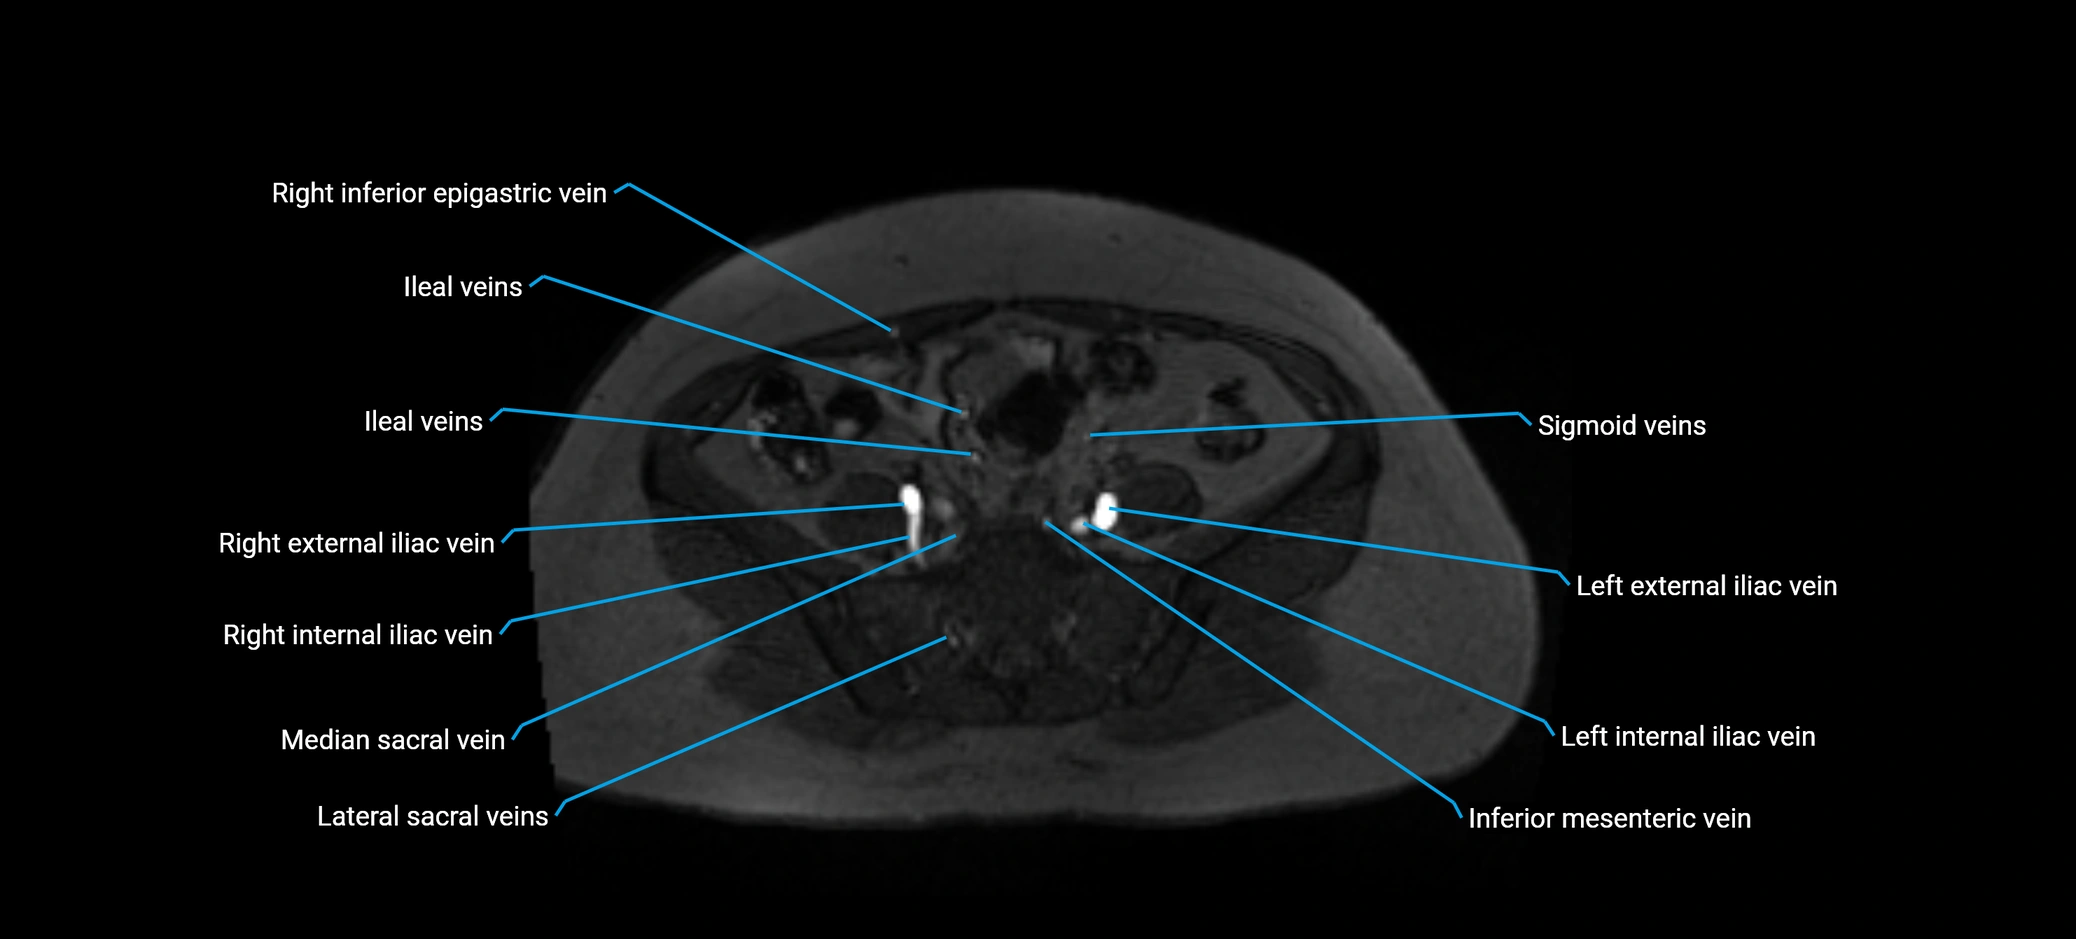

MRI image

image